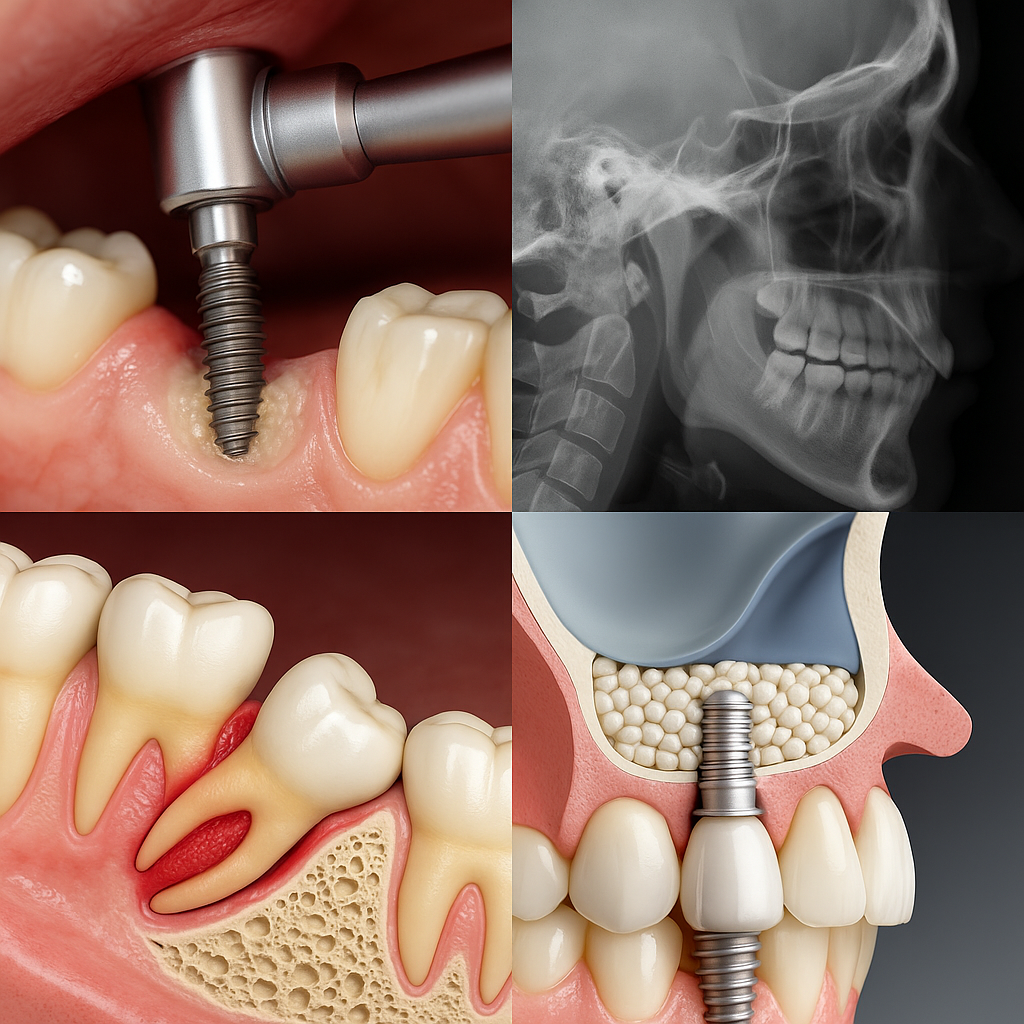

جراحیهای مرتبط با استخوان فک، دندانهای نهفته، ترمیم بافت استخوانی، کاشت ایمپلنت پیشرفته و درمان بیماریهای مفصل گیجگاهی فکی (TMJ)، تنها بخشی از گستره کاری متخصص فک و صورت است. در این مقاله، به دلایل اصلی نیاز به این تخصص و موقعیتهایی که مراجعه به آن ضروری است میپردازیم.

۴. کاشت ایمپلنتهای پیچیده

اگر استخوان فک بهاندازه کافی وجود داشته باشد، کاشت ایمپلنت را میتوان در کلینیک انجام داد. اما در بسیاری از بیماران، بهدلایل مختلف مانند تحلیل استخوان بعد از کشیدن دندان، یا بیماریهای پریودنتال، ایمپلنت با پیچیدگیهایی روبهروست:

در این موارد جراح فک و صورت وارد میشود:

- کمبود شدید تراکم یا حجم استخوان

- نیاز به زاویهگذاری دقیق ایمپلنت

- شکست ایمپلنت قبلی و نیاز به برداشت آن

- ترمیم همزمان بافت استخوانی و نرم (لثه)

در این شرایط، یک ایمپلنت ساده به جراحی بازسازی فک تبدیل میشود که فقط متخصص میتواند آن را بهدرستی انجام دهد.

۵. سینوس لیفت (Sinus Lift)

در فک بالا، بهویژه ناحیه مولرها (دندان ۶ و ۷)، سینوس فکی در نزدیکی دندانها قرار دارد. اگر استخوان کف سینوس تحلیل رفته باشد، جراح مجبور به بلند کردن کف سینوس و افزودن استخوان مصنوعی یا طبیعی برای کاشت موفق ایمپلنت میشود.

سینوس لیفت شامل:

- باز کردن دریچه به سینوس ماگزیلاری

- بالا بردن غشای سینوس بدون پارگی

- افزودن پودر استخوان (گرافت)

- بستن ناحیه با دقت کامل

هرگونه آسیب به غشای سینوس میتواند منجر به عفونت سینوسی یا شکست کاشت ایمپلنت شود. به همین دلیل، این جراحی فقط باید توسط متخصص فک و صورت انجام شود.

۶. استفاده از پودر استخوان (Bone Graft)

در مناطقی که استخوان فک تحلیل رفته باشد، برای حفظ ایمپلنت یا بازسازی استخوان، از پودر استخوان (Synthetic/Allograft/Xenograft) استفاده میشود.

جراح فک و صورت با بررسی آناتومی بیمار، بهترین نوع گرافت را انتخاب میکند و آن را با دقت در محل موردنظر قرار میدهد تا استخوانسازی جدید تحریک شود.